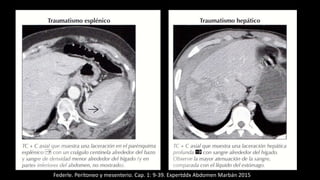

Hemoperitoneo

Federle. Peritoneo y mesenterio. Cap. 1: 9-39. Expertddx Abdomen Marbán 2015

Paciente de 35 años con abdomen agudo. La TC con contraste muestra acumulación de fluido de

alta densidad compatible con hemoperitoneo por ruptura de aneurisma de la arteria esplénica.